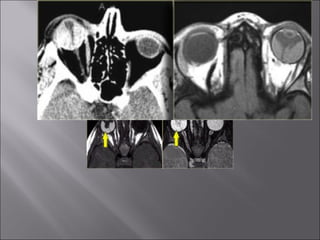

Ultrasound and CT scans provide anatomical images of the orbit, while color Doppler imaging provides visualizations of vascular structures and blood flow within lesions. These imaging techniques are used to evaluate a variety of orbital conditions involving blood vessels, infections, tumors, congenital issues, trauma, and more, and can help identify vascular disorders, thrombosis, treatment responses, and dynamic changes in benign tumors over time.